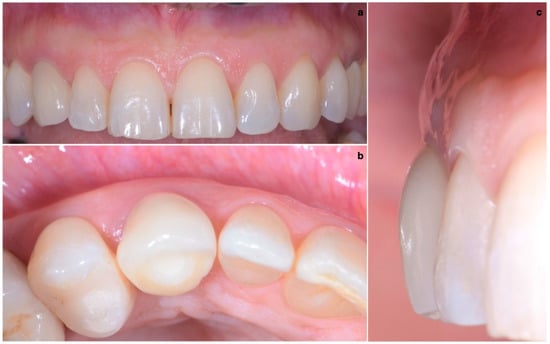

A 40-year-old patient presented with an endodontic fistula on the maxillary right canine (Figure 1a–c). Radiographic evaluation revealed internal root resorption (Figure 2). The medical history did not include any systemic conditions contraindicating implant placement or regenerative surgery. The patient did not suffer from any form of periodontal disease. Due to the extension of root resorption, the tooth was considered irrational to treat, and the treatment plan consisted of extraction and immediate implant positioning.

Figure 1. (ac) Forty-year-old patient with endodontic fistula on maxillary right canine.